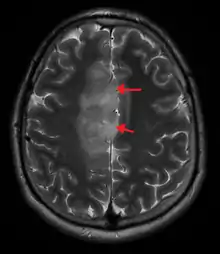

| Oligoastrocytoma | |

| A oligoastrocytoma on CT | |

An X-ray computed tomography (CT) or magnetic resonance imaging (MRI) scan is necessary to characterize the anatomy of this tumor as to size, location, and its heter/homogeneity. However, final diagnosis of this tumor, like most tumors, relies on histopathologic examination (biopsy examination).[3]